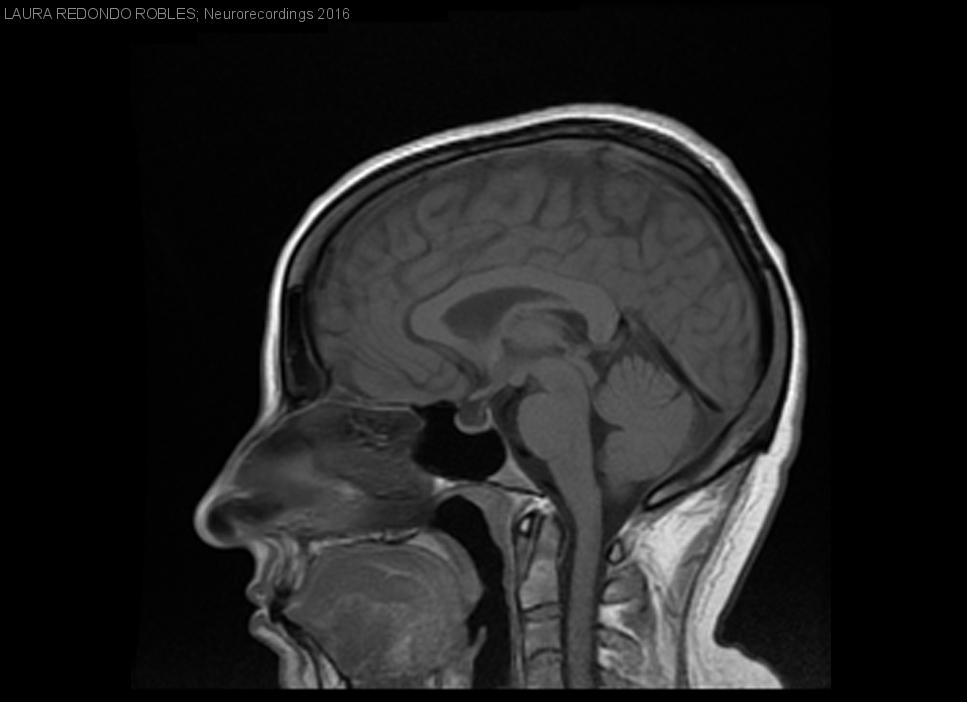

Diagnóstico final: Hipertensión intracraneal idiopática

Paciente de 34 años de edad que acudió a urgencias por cefalea holocraneal y pérdida visual progresivas de cinco meses de evolución además, asociaba un aumento de 10 kg de peso en los últimos seis meses....